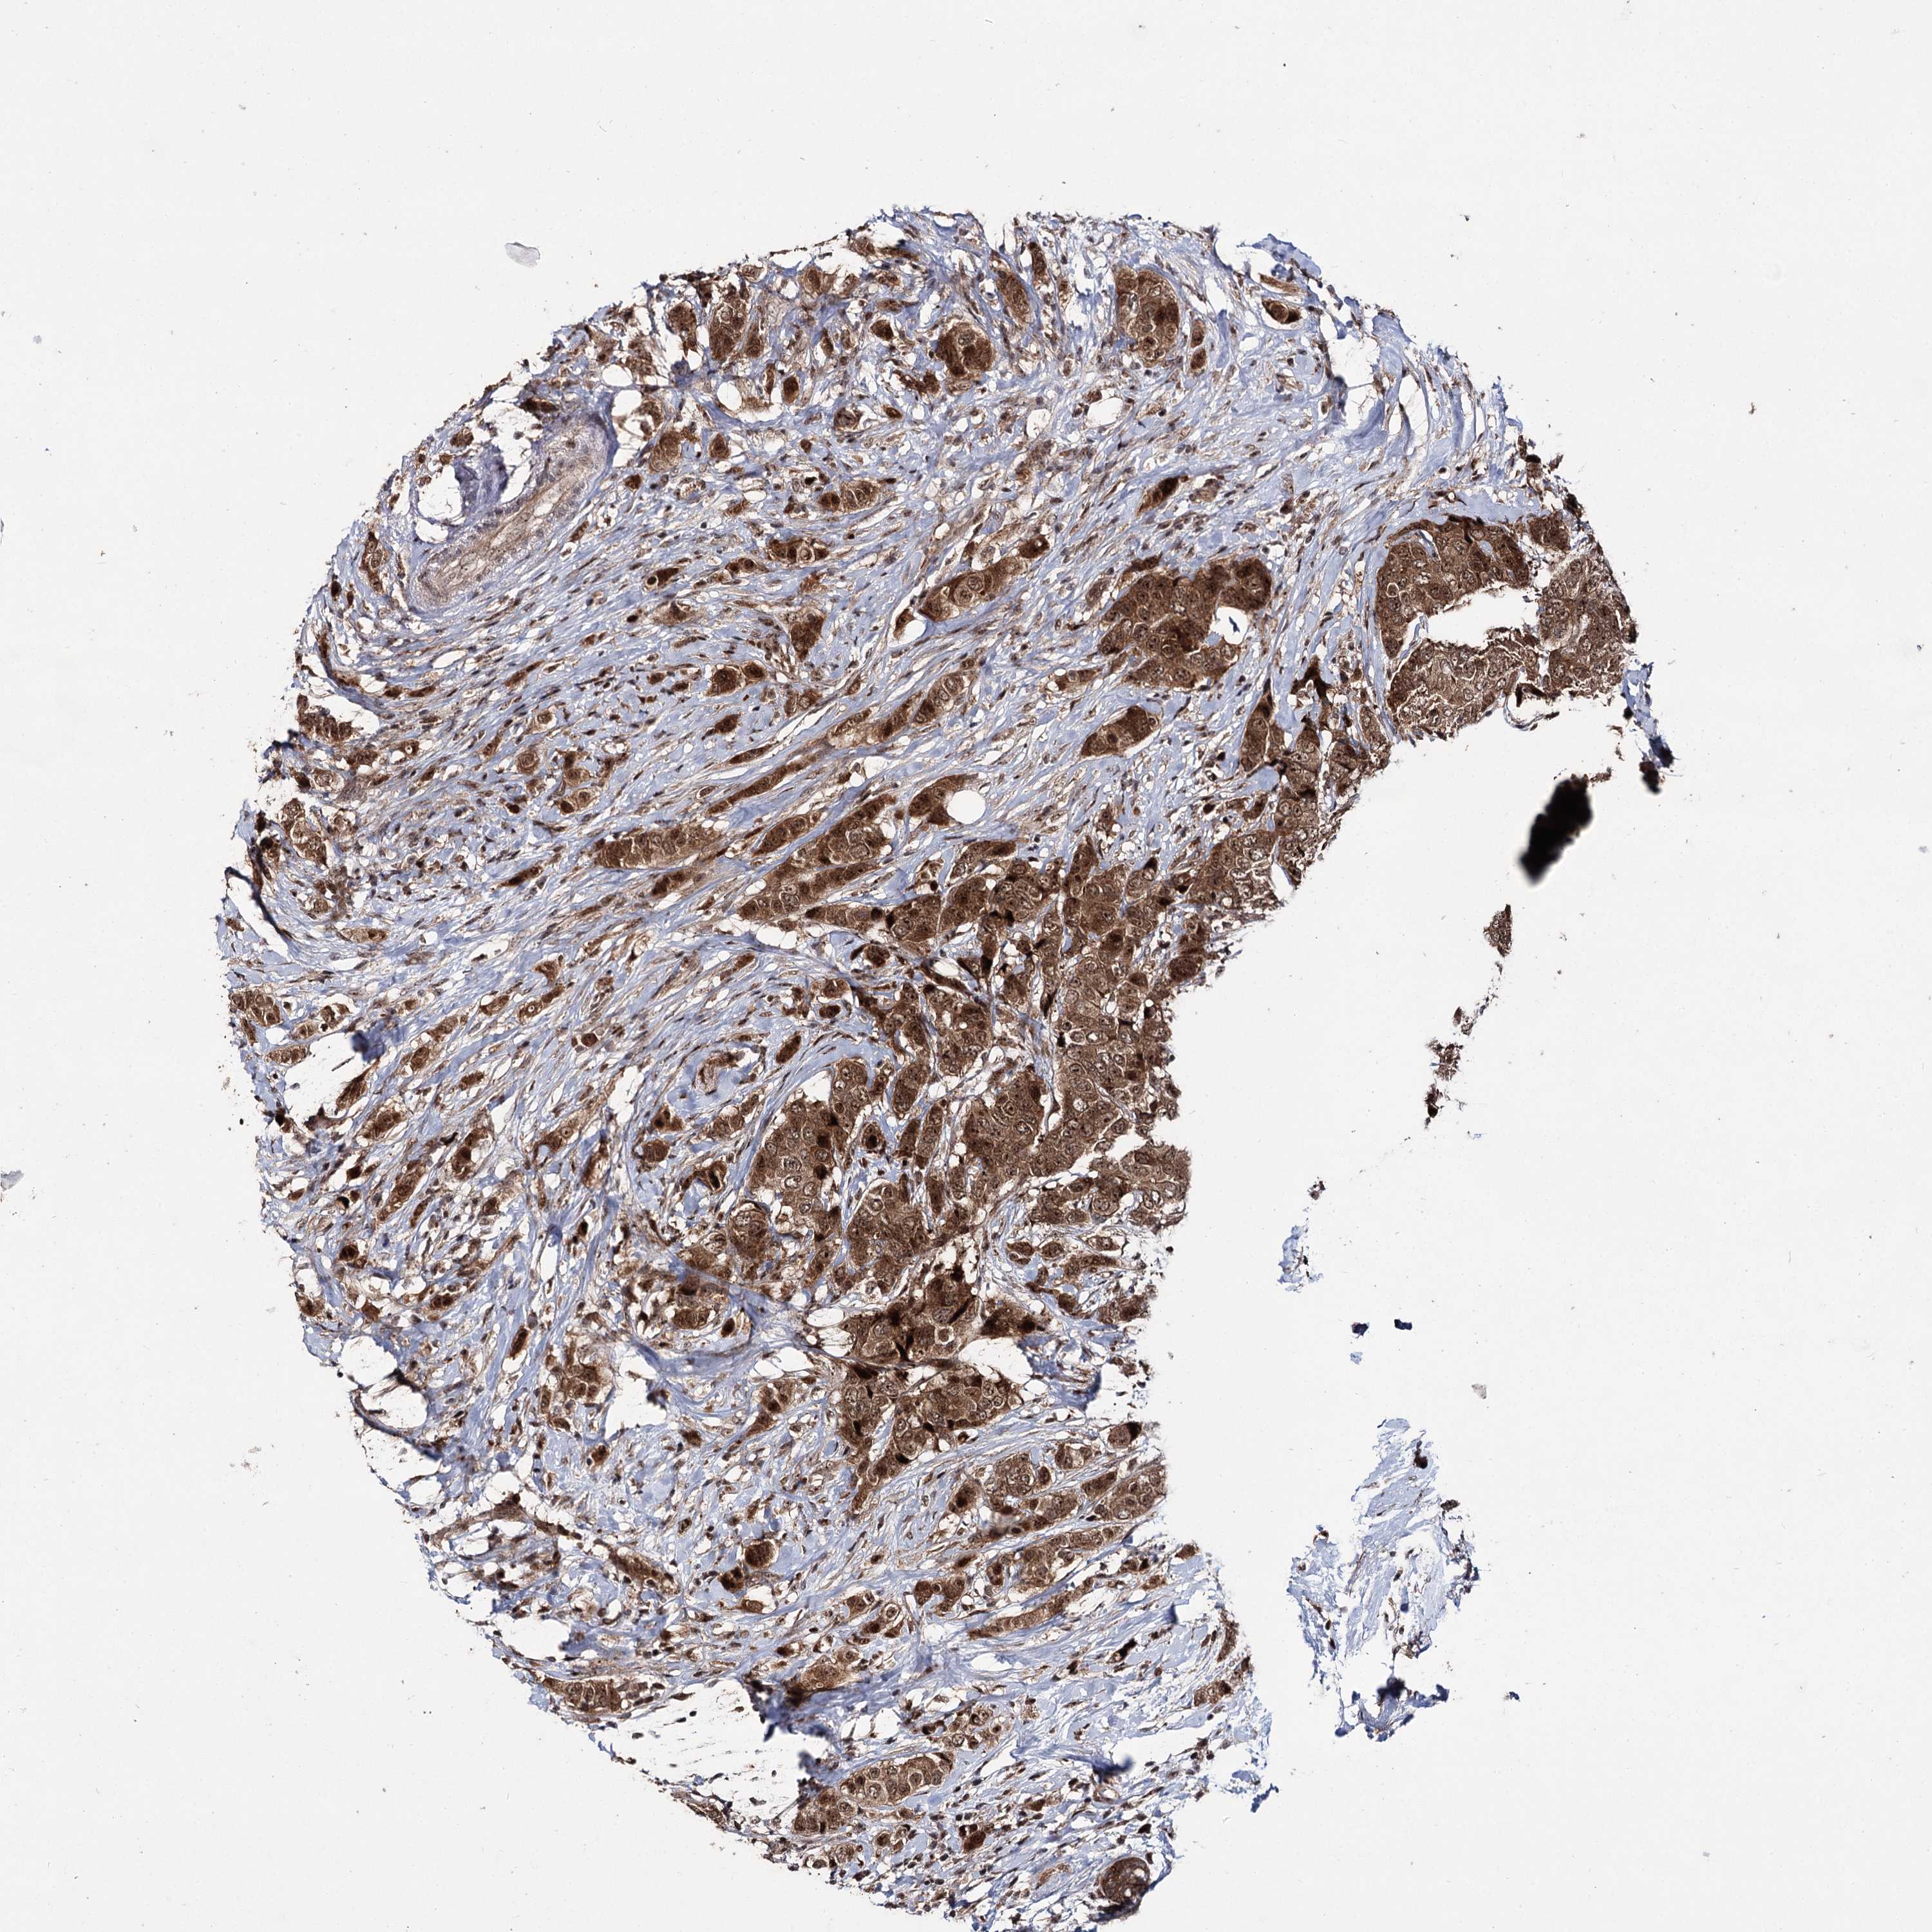

BRCA TCGA BRCA VALIDATION PROTEIN EXPRESSION

Breast cancer

Human cancer

Breast invasive carcinoma